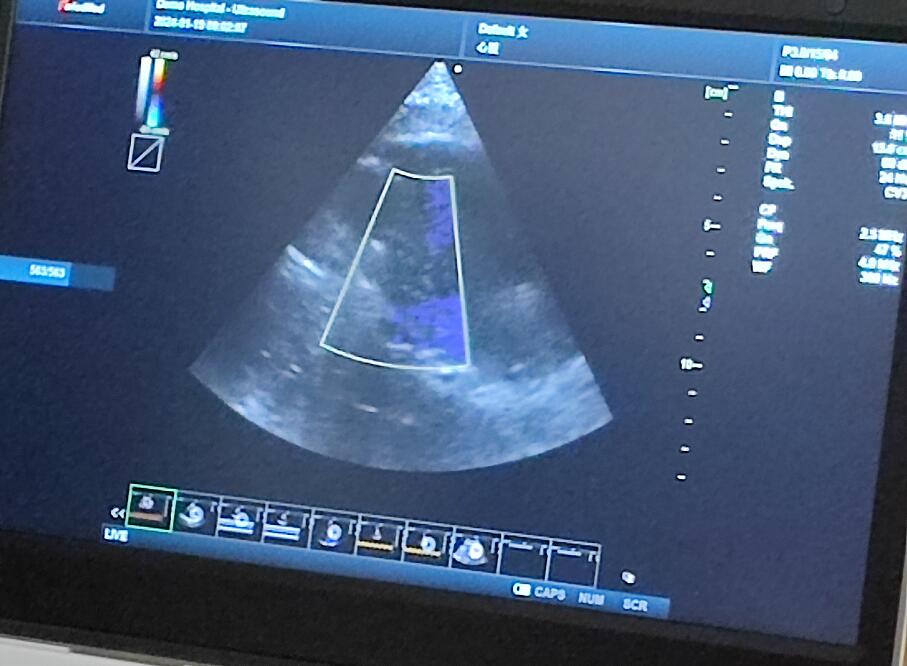

當天的超聲培訓現(xiàn)場氣氛熱烈非凡,來自普邁思醫(yī)療事業(yè)部的同仁們紛紛積極參與,滿懷期待地聚集在講臺周圍,他們的眼神充滿了對新知識的渴望和對技術提升的執(zhí)著追求。老師身邊里三層外三層圍滿了學員,大家或是聚精會神聆聽講解,或是踴躍提問,交流互動,濃厚的學習氛圍讓整個場地顯得熱鬧非凡,盡管空間狹小,但阻擋不住的是每一位參與者內(nèi)心深處對于專業(yè)技能提升的決心與毅力。

授課的專家老師被這股澎湃的學習熱情深深打動,她的臉上洋溢著欣慰和鼓舞的笑容。面對這樣一群如饑似渴的學子,老師更是傾盡全力,毫無保留地將自己豐富的臨床經(jīng)驗和深厚的專業(yè)理論知識悉數(shù)傳授,詳細解答每一個問題,用心指導每一次操作演練。她表示,普邁思醫(yī)療事業(yè)部團隊展現(xiàn)出的這種敬業(yè)精神和積極向上的風貌讓她深受感染,還給予了他們高度評價和嘉許。